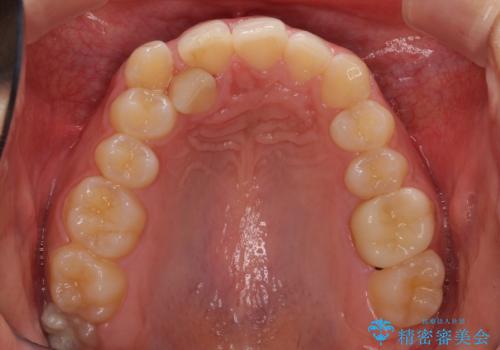

- 上顎の重なっている前歯を気にして来院された患者様です。

八重歯改善には抜歯が必要で、八重歯の移動量が多く、更には右側にずれている正中を改善する必要がありました。

インビザライン単体での治療は困難と判断し、補助装置により八重歯移動後にインビザラインを用いることとしました。